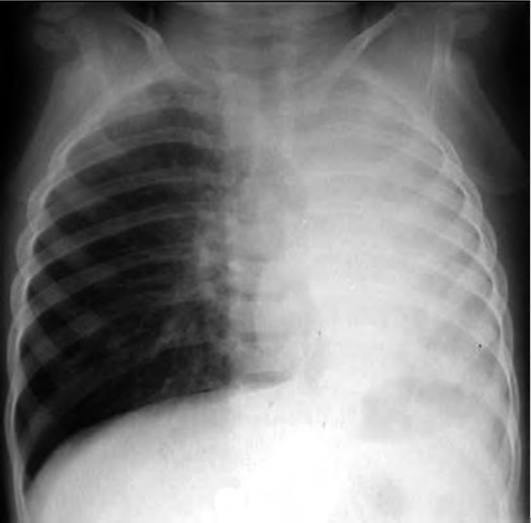

Рентгенография не относится к стандартным методам исследования, однако ее следует проводить при отсутствии ответа на лечение для исключения пневмоторакса, сопутствующих заболеваний легких. В приступном периоде БА у детей раннего возраста на рентгенограмме грудной клетки отмечают резкое эмфизематозное вздутие легких, горизонтальное положение ребер, широкие межреберные промежутки, усиление сосудистого рисунка, расширение легочных корней. Во время приступа БА преимущественно субсегментарные ателектазы, которые обычно быстро расправляются, выявляют у 6-7% больных (рис. 3-6).

image

Рис. 3-6. Рентгенограмма грудной клетки: ателектаз верхней доли правого легкого во время приступа бронхиальной астмы